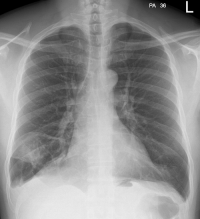

| A | Assess Quality Airway | • PA v AP • Count post ribs - 11 for good insp. • Rotation - vertebral spines equally b/w medial clavicle ends |

| B | Bones soft tissues | • symmetry, fractures, osteoporosis, and lesions. • soft tissues for foreign bodies, swelling, and subcutaneous air. |

| C | Cardiac | • should be <50% of the chest diameter on PA films and <60% on AP films. • Check for the heart shape, calcifications, and prosthetic valves. |

| D | Diaphragm | • shape may be flat with COPD,tension pneumothorax •R higher than L • look for free gas below |

| E | Effusions Extra-thoracic | • costo-phrenic angles for sharpness |

| F | Fields Fissures FB | • masses, consolidation, vessels, bronchograms • ?fluid in fissures, change of position • FB's- ETT, CVC, NG tubes, other |

| G | Great vessels Gastric bubble | • aortic knuckle size and shape • gastric bubble not displaced? |

| H | Hilar mediastinum | • LNs, Ca++, masses • widening - suggestion of dissection • displacement - suggestion of mass • angle of main bronchi - suggestive of collapse, masses • L hilum should NEVER be lower than R |